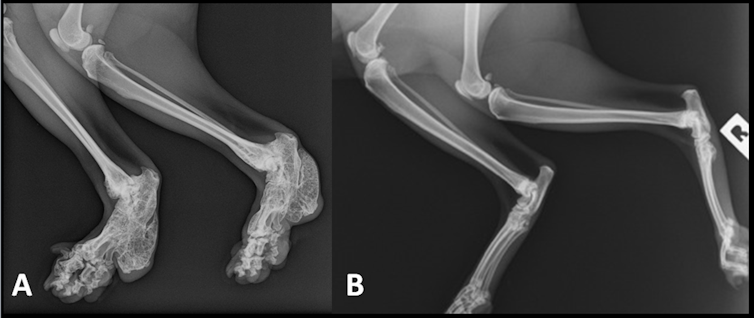

It didn’t take long for veterinarians and scientists to figure out that if the cartilage in the ear was defective, then cartilage in the joints might also be dodgy. The British geneticist Oliphant Jackson demonstrated this unequivocally in a most elegant series of classic genetic and radiological experiments in a hospital basement in the 1970s.

In the early 1990s a group of Australian veterinarians demonstrated convincingly that all Scottish Fold cats have abnormal bone development of their distal limbs. This is generally associated with early onset and accelerated progression of osteoarthritis (degenerative joint disease) in joints of the distal limbs and tail. The ankle and wrist were the joints most obviously affected, especially the ankles.

Scottish Folds have shortened limbs, an abnormal gait, a peculiar and sometimes stiff or painful tail, and the propensity to develop osteoarthritis at an earlier age. This causes variable lameness (often severe) and secondary deformity.